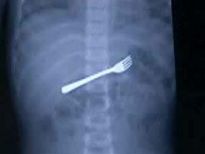

Şoke eden röntgen filmleri

Bu röntgen filmleri görenleri şaşkına çeviriyor!